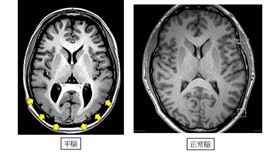

全球只有13病例 平腦症大腦無皺褶

正常人的大腦表面會有許多皺褶,稱之為腦迴,和高階認知...